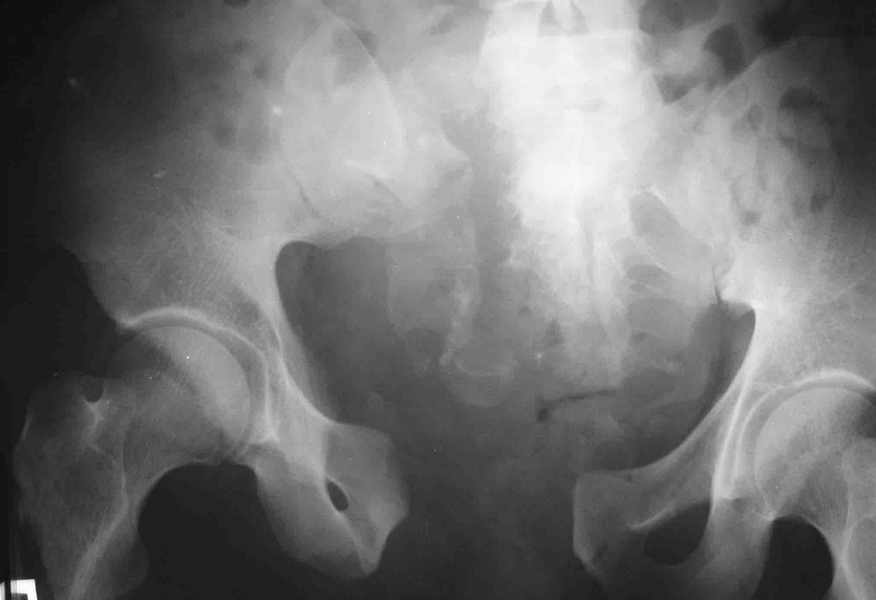

извините за опоздание , вот фотографии

<На R-мме таза ( в прямой проекции, вход и выход из таза) определяется изолированный разрыв лонного сочленения с диастазом 4см,расширение щели правого КПС(вертикальной нестабильности нет, >

В представленном случае повреждение несомненно ротационное и реальный диастаз как раз около пограничных 2,5 см, репозиция идеальная, достигнута в первые дни после травмы. Я бы ограничился 3 мес фиксации в аппарате с ограничением нагрузки первый месяц, и функциональными снимками в 6 -8 недель.